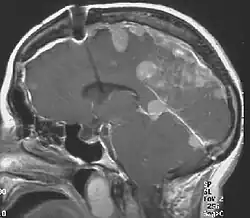

- Hörnerv: Wie schon erwähnt findet man bei 90 % der Betroffenen bei einer Kernspintomographie des Schädels ein beidseitiges Akustikusneurinom.

Das Kern- oder Kardinalsymptom der Erkrankung sind die beidseitigen gutartigen Tumoren des Hörnervs (sog. bilaterale Akustikusneurinome). Durch dieses Symptom ist die Krankheit definiert.

- Der Nachweis von bilateralen Akustikusneurinomen mittels bildgebender Verfahren.